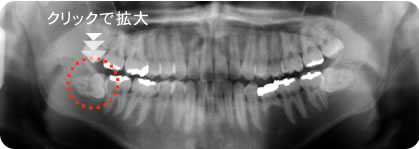

親知らず 写真

横向きに埋まっている親知らずを見事な手つきで本当に10分くらいでなんなく抜歯していただきました。先生ありがとうございました!